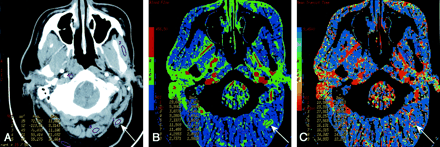

Patient 3 with surgically treated acinic cell cancer of the parotid gland.

A, Rater 1. Contrast-enhanced neck CT scan shows a mass in the suboccipital subcutaneous fat (arrow) that was a suspected metastatic lymph node. Histology showed fat necrosis and chronic inflammation. ROIs are placed on the lesion (1) and on the masseter (3) and paraspinal (5) muscles.

B, Rater 2. CTP functional map shows relatively low blood flow of 24.9 mL/100 g/min in the lesion (arrow, ROI 1) and shows ROIs in the masseter (4) and paraspinal (8 and 9) muscles. Scale from red to blue corresponds to decreasing flow.

C, Rater 2. CTP functional map shows that the lesion (arrow, ROI 1) has a relatively long MTT of 10.5 seconds and shows ROIs in the masseter (4) and paraspinal (8 and 9) muscles. Scale from red to blue corresponds to increasing MTT.